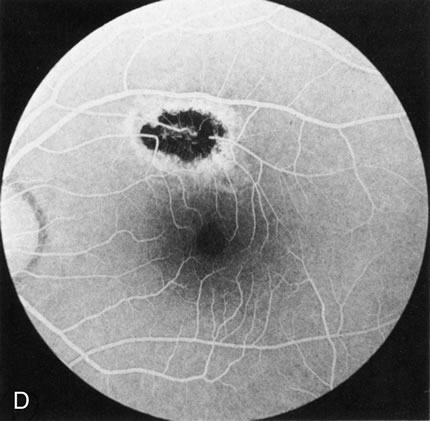

HEREDITARY HEMORRHAGIC MACULAR DYSTROPHY (PSEUDOINFLAMMATORY MACULAR DYSTROPHY OF SORSBY)

FA plays an important role in the understanding of this rare disorder. In the earliest manifestations of the disease, FA shows a single, isolated choroidal neovascular membrane unassociated with other causes of a membrane, such as drusen or angioid streaks (Fig. 13).25 Presumably this membrane is the cause of the subsequent hemorrhagic maculopathy with secondary disciform scarring, occurring initially in the macula but often extending throughout the retina.

Fig. 13. Hereditary hemorrhagic macular dystrophy (pseudoinflammatory macular dystrophy of Sorsby). Fluorescein angiography in this family member demonstrates that the earliest finding is an isolated choroidal neovascular membrane B). Despite laser photocoagulation, a hemorrhagic maculopathy developed in this eye (C, D) and eventually a disciform scar (E) formed, as it had in the fellow eye, and in the eyes of other affected family members.

Abnormal choroidal perfusion, manifested on FA as a delay in choriocapillaris filling, has been seen in the restudy of some of Sorsby's initial pedigrees.26 This unusual pattern has been related to the histopathologic finding of a “confluent, lipid-containing, amorphous deposit found between the basement membrane of the RPE and the inner collagenous layer of Bruch's membrane.”27